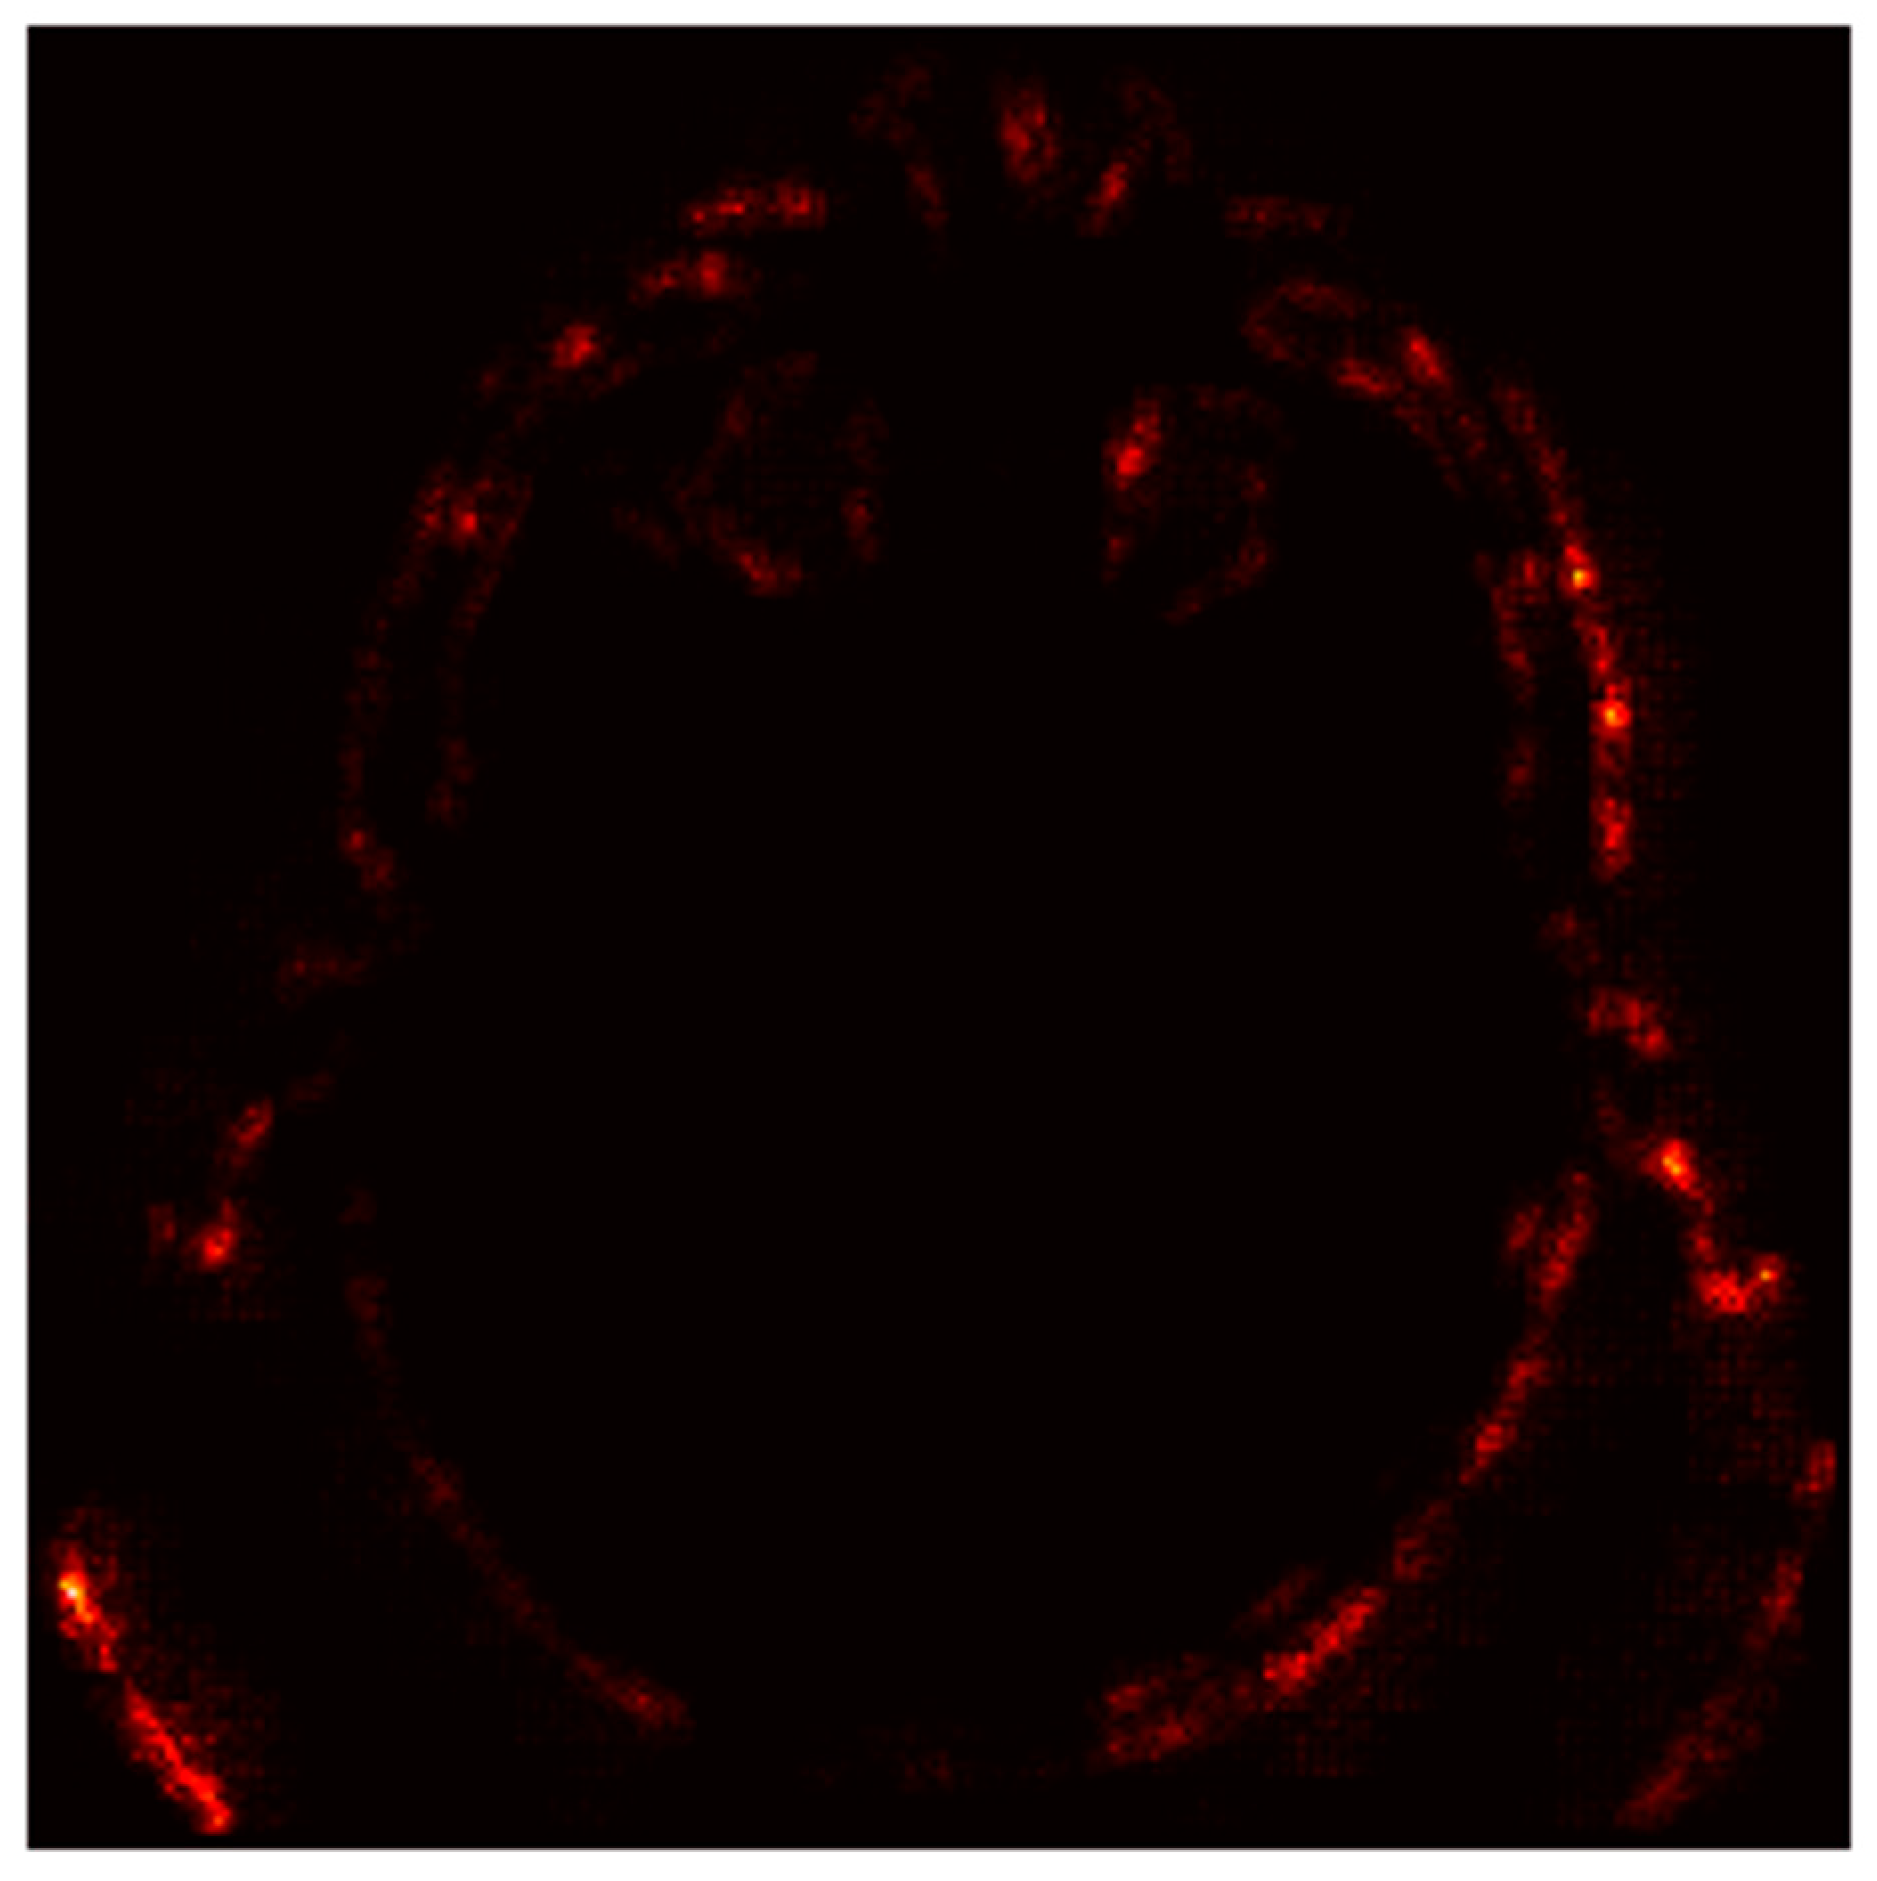

4.6.3. Gradient-Based Saliency Maps

- Red Areas: These regions, such as the hyperdense clot in the left hemisphere, are critical for the “Stroke” prediction. The model assigns high importance to these areas, aligning with clinical expectations that hyperdense regions indicate hemorrhagic strokes.

- Green/Blue Areas: These regions have minimal impact on the prediction, indicating that the model focuses on specific anatomical features rather than the entire image.

- Bright Spots (High Gradients): These regions correspond to areas where small changes in pixel values significantly alter the model’s output. For instance, the hyperdense clot (bright spots) is highlighted as a critical region for the “Stroke” prediction.

- Dark Regions (Low Gradients): These areas, such as the background or non-stroke-related anatomy, have little to no impact on the prediction, confirming the model’s focus on stroke-prone regions.